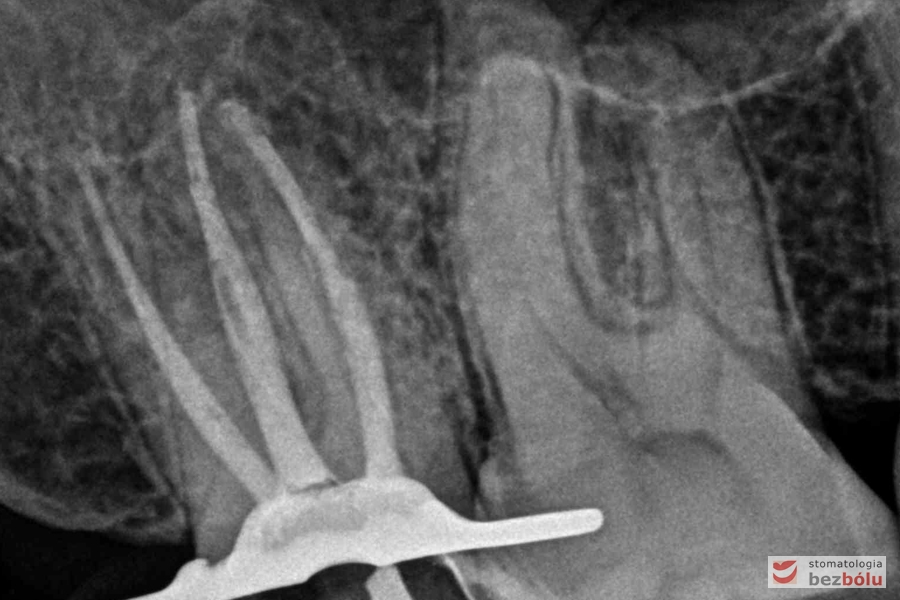

Kontrola radiologiczna - ocena szczelności wypełnionych kanałów korzeniowych

Kontrola radiologiczna – ocena szczelności wypełnionych kanałów korzeniowych